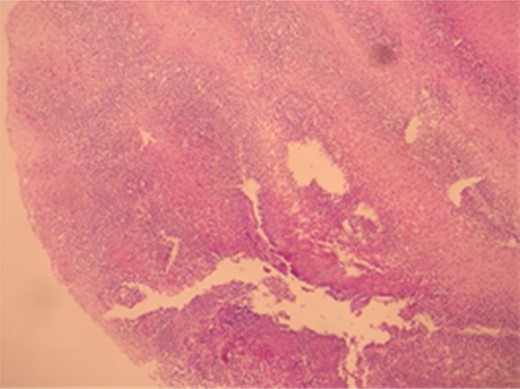

A male patient of 35 years age presented to our General Surgery Clinic with complaints of difficulty in swallowing, sensation of food sticking in the back of the breast while eating, stomach ache, weight loss and weakness for nearly a year. The fact that the symptoms chiefly arose upon ingestion of dairy products was interesting. Normal values were obtained for complete blood count serum CRP, sedimentation and total serum IgE of the patient. Standing abdominal X-ray and abdominal ultrasonography failed to reveal any evidence of pathology. Mucosal fissure and erosional areas were observed in the middle distal esophagus using upper GI endoscopy and are probably associated with reflux esophagitis; biopsies were made of the same (Fig. 1). Bulbitis and pangastritis were observed in the duodenum and stomach and biopsies were made. Pathological examinations of the endoscopic biopsies revealed evidence of chronic esophagitis in esophagus, chronic Helicobacter pylori-positive pangastritis in stomach and chronic duodenitis in the duodenum. The examination showed eosinophilic infiltration only in the esophagus (Fig. 2). Histological examination (40 X) revealed more than 30 eosinophils per field (Fig. 3). The patient was diagnosed with eosinophilic esophagitis and administered dexamethasone I.M as well as treatment for H. pylori eradication which resulted in relief of the symptoms. The patient was also instructed to avoid consumption of milk and dairy products, which caused the development of symptoms. The control endoscopic examination and pathological evaluation made after 3 months, failed to reveal evidence of esophageal eosinophilic infiltration, relapse did not occur during the following 2 years.

The image of linear erosional areas in middle and distal esophagus.